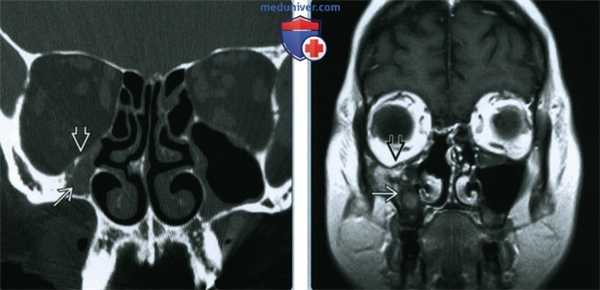

(Слева) При корональной КТ пазух у пациента 31 года с носовыми кровотечениями и ОГПН определяется снижение пневматизации левой верхнечелюстной пазухи за счет мягкотканного содержимого и ее вздутие. Определяется также резорбция дна левой орбиты с легким пролабированием ОГПН в орбиту, и полная эрозия внутренней стенки и перегородки.

(Справа) При аксиальной МРТ Т2 FS у этого же пациента визуализируется неоднородное объемное образование в левой верхнечелюстной пазухе с фокальным нарушением целостности передней стенки и полной эрозией внутренней стенки с распространением образования в полость носа и носоглотку.

(Слева) При аксиальной МРТ Т1 у этого же пациента визуализируется изоинтенсивное образование, приводящее к вздутию левой верхнечелюстной пазухи. Разрозненные зоны гиперинтенсивного (Т1) сигнала свидетельствуют о недавнем кровоизлиянии.

(Справа) При аксиальной МРТ Т1 С+ FS у этого же пациента в левой верхнечелюстной пазухе и полости носа визуализируется крупная экспансивная ОГПН.